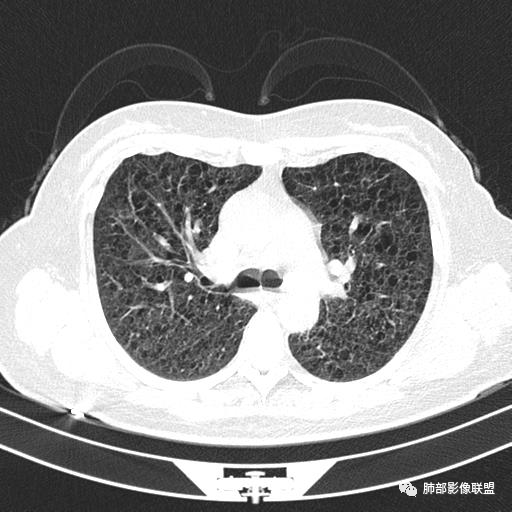

中年女性,不吸烟

双肺弥漫囊腔,累及肋膈角,囊腔形态相对规则单一。

CT平扫示双肺弥漫分布大小不等囊状薄壁透光区,无内、中、外带分布差异,间质稍示增厚。拟LAM

中年女性育龄期妇女,咳嗽气喘,无吸烟史,有苯吸入史。影像:双肺弥漫均匀小囊腔,无明显分布优势,囊腔形态欠规则,壁薄,部分囊腔边缘血管征,伴双肺弥漫磨玻璃影,无结节,考虑lam,鉴别苯中毒肺损伤,囊腔多有分布优势,小叶中心分布为主,形态规整等

女,46,活动性气喘1年。苯吸入史半年。胸部CT:两肺弥漫囊腔,上至肺尖,下至肋膈角,形态类似小囊腔。考虑:LAM,鉴别LIP,BHD,PLCH等。

双肺弥漫大小不一薄壁含气囊腔,囊间肺组织正常,正常肺背景,肺尖肺底受累;青年女性,气喘,支持LAM

双肺多发大小相近的囊状影,分布趋势趋于一致,中年女性,考虑LAM。部分囊内见血管及分隔影,小叶中心性肺气肿代排

CT表现:双肺弥漫大小不等的薄壁囊腔,囊壁<2mm,外形规则,血管影多位于囊腔周围,囊腔之间肺组织正常,随着疾病进展到晚期,囊腔变大、增多,不可胜数,囊腔可融合成较大的囊,与肺气肿相似,形成间质性肺纤维化。部分病例可出现结节影。